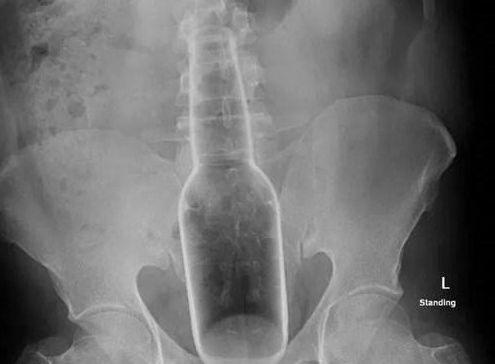

日前,东莞市某医院接收了一名特殊的患者,医生在看完男子的情况后也感到惊讶不已。据了解,男子文先生(化名)因感到肛门处瘙痒,就用花露水瓶子进行挠痒,结果不慎将整个花露水瓶都塞进了体内,这让文先生感到非常的害怕。之后,文先生便出现了不适,其腹部开始疼痛难忍,这时他不得不紧急到医院就诊。文先生到达医院后也顾不得尴尬,将事情发生的全过程告诉了医生,医生在拍片子了解后对文先生进行了手术。在医生的努力下,从文先生的体内成功取出一个长约18厘米、直径5厘米的花露水瓶。